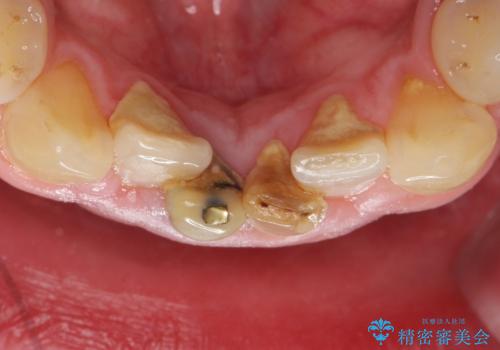

- 下の前歯の色が気になることを主訴に来院された患者様です。

下の前歯は金属の土台により黒くなり、隣の歯も神経が死んで暗く変色していました。

神経が死んでいる歯の根管治療を行った後、セラミッククラウンによる補綴治療を行いました。

- ¥320,000 (根管治療×1、土台×2、仮歯×2、クラウン×2)費用は治療当時の料金となります